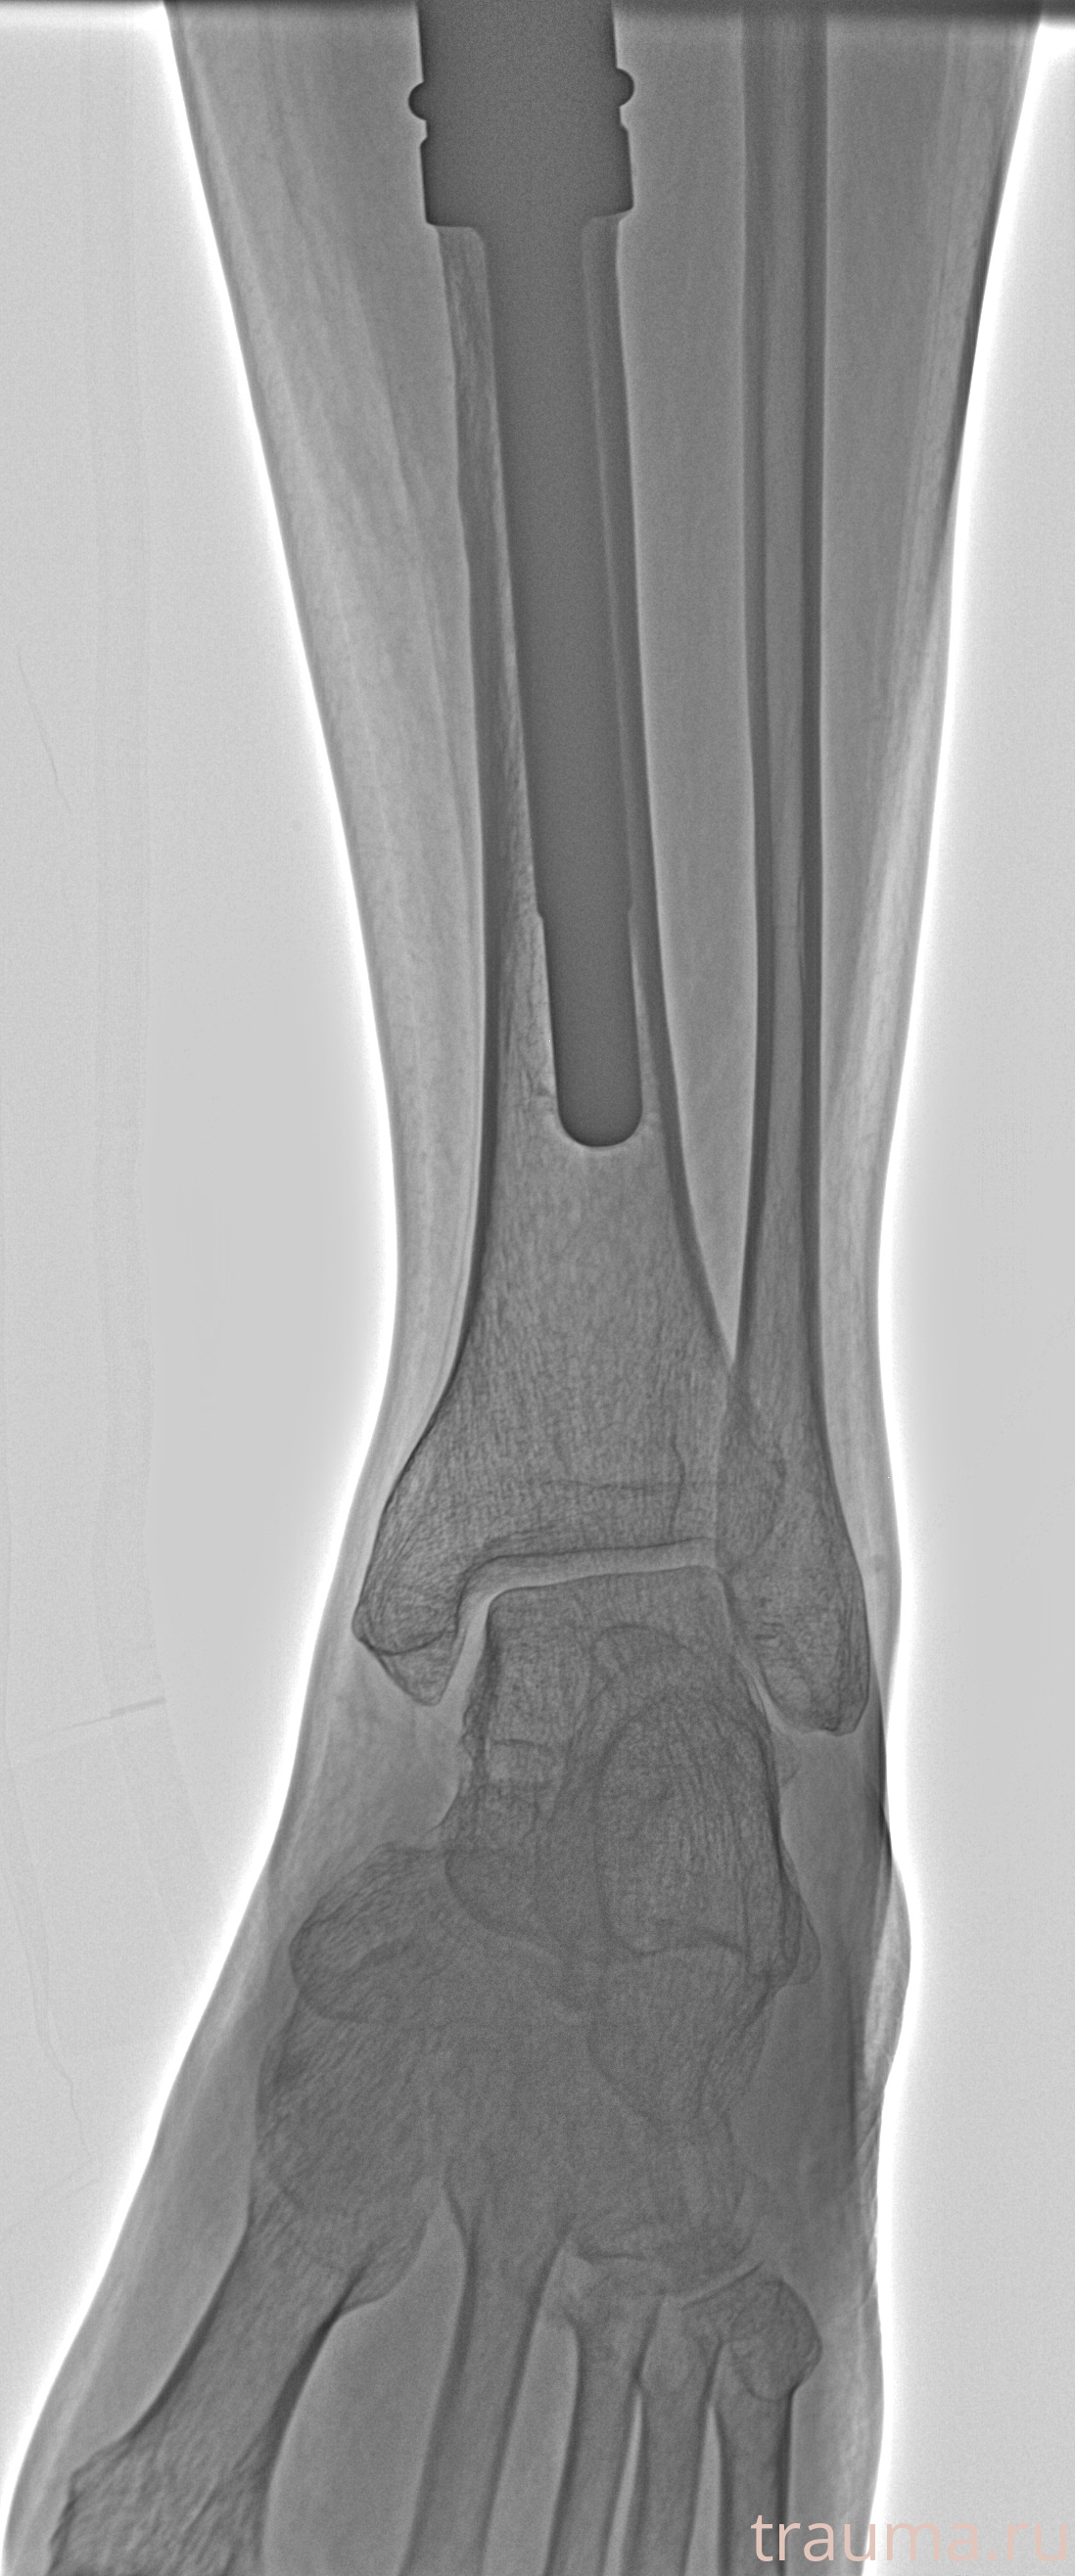

Рентгенограммы

Рентген на дому: по вашему адресу приезжает врач-рентгенолог, травматолог-ортопед с мобильным рентгеновским аппаратом, проводит диагностику травмы или заболевания, делает необходимые рентгенограммы, дает рекомендации по дальнейшему лечению. Получить качественные снимки в домашних условиях возможно благодаря уникальной методике, разработанной МосРентген Центром для института  Склифосовского